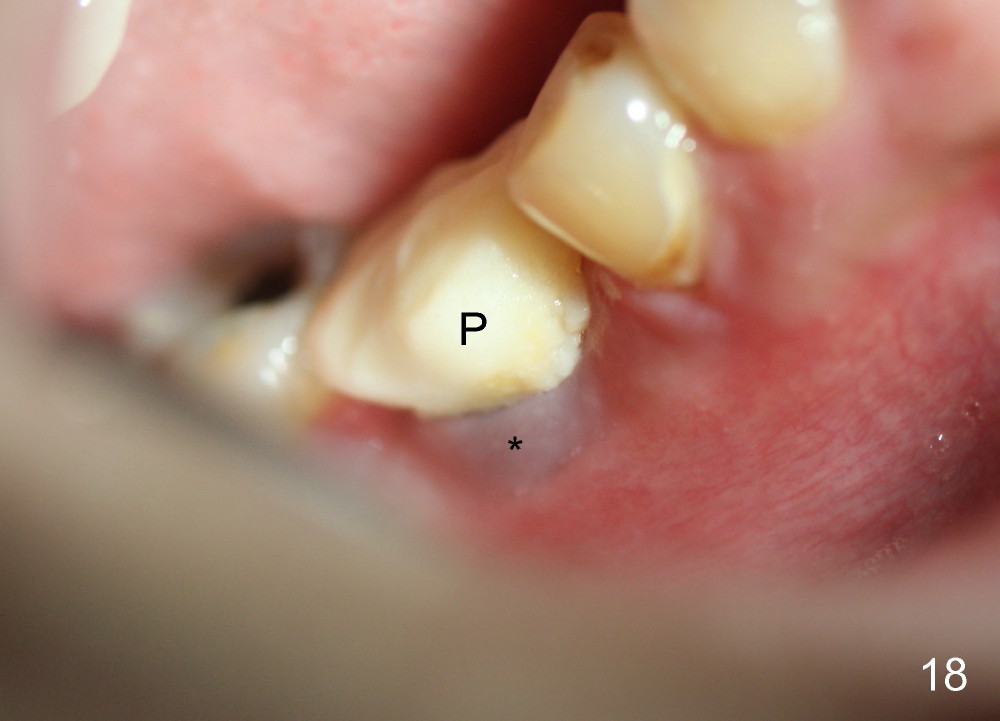

A 38-year-old lady agrees to have implant placement 7 years after loss of the crown of the lower right first molar (Fig.1,2). When the tooth is extracted, the septum is found to be low (Fig.3,4). To confirm it, a PA is taken (Fig.5). To initiate an osteotomy in the septum, it is trans-sectioned with thin osteotomes as shown in Fig.4 insert (black line). A 2 mm pilot drill is placed in the septum (Fig.6: P). The osteotomy is enlarged by 2.5-4.0 mm reamers (Fig.7,8), followed by insertion of 6x17 mm tapered tap at the depth 14 mm (Fig.9). The osteotomy is further enlarged by 4.5 and 5.0 mm reamers. A 6.0x14 mm one piece implant is placed initially. The trajectory is not ideal. A 6.0x14 mm one piece implant is placed initially. The trajectory is not ideal. The implant is removed from the osteotomy partially and reinserted with improved trajectory (Fig.11, compare to Fig.10 (red line)). Primary stability is high. There is not much bone mesiodistally so that the trajectory is easily changed in that direction. After abutment preparation, mixture of autogenous bone (harvested from reamers) and allograft is placed in the residual mesial and distal sockets (Fig.12). To contain the bone graft, an immediate provisional is placed (Fig.13 P). The occlusal plane of the provisional is significantly lower than that of the adjacent teeth to avoid micromovement of the implant. The patient is advised to eat soft food on the left side. Six days postop, the patient returns for prophy. The provisional is removed; the bone graft appears to be incorporating into the socket (Fig.14). After recementation, the provisional remains in place for 3.5 months; PA shows increased bone density in the mesial and distal sockets (Fig.15, compare to Fig.5,11). Due to insurance coverage, the patient defers fabrication of definitive restoration for at least 7 months. The immediate provisional is finally lost 8.5 months postop: the gingiva attaches to the 1-piece implant (Fig.16), while the density of the mesial socket increases (Fig.17 *) with formation of the cortex (lamina dura) coronally (v). Before the provisional (Fig.18 P) is removed for cementation of the definitive restoration, black shadow (*) is noted over the buccal gingiva. It is partially due to buccal placement (Fig.19) and partially due to buccal atrophy over a period of 10.5 months postop. How to prevent buccal placement? Positioning the first pilot drill in the septum buccolingually is a key. Eleven months post crown (Fig.20 C) cementation, the black shadow remains, but there is no tenderness. If the implant threads are immediately underneath the periosteum, there is tenderness.